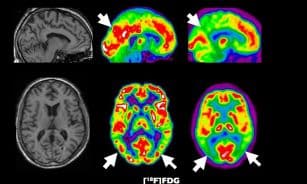

Sveikata Sugrąžins atmintį: mokslininkai atskleidė, kaip paprastas purškalas atjaunina smegenis Ieva Kazlauskaitė • 2026-04-26